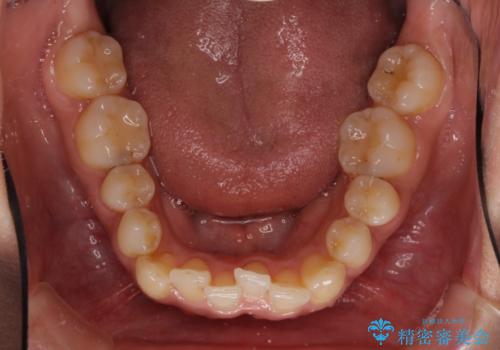

- 定期的に東京に来るので、沖縄から矯正治療で通院したいとのことで来院された患者様です。

歯列不正は軽度であったので、応急処置の少ないインビザラインにて矯正治療を行うこととしました。

通院途中に、仕事の都合で東京に来る機会が激減してしまったため、なかなか治療が進まず、当初終了予定であった時期が2年近くずれ込んでしまいました。